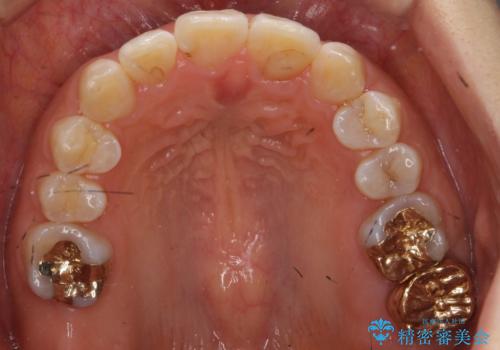

銀歯も白くということでしたので虫歯治療も一緒に行っています。

左上7の根の治療や左下56銀歯の治療なども行いました。

右下7は根管治療をおすすめしましたが、患者様のご希望により抜歯となり、そのスペースを利用して下の前歯をならべています。